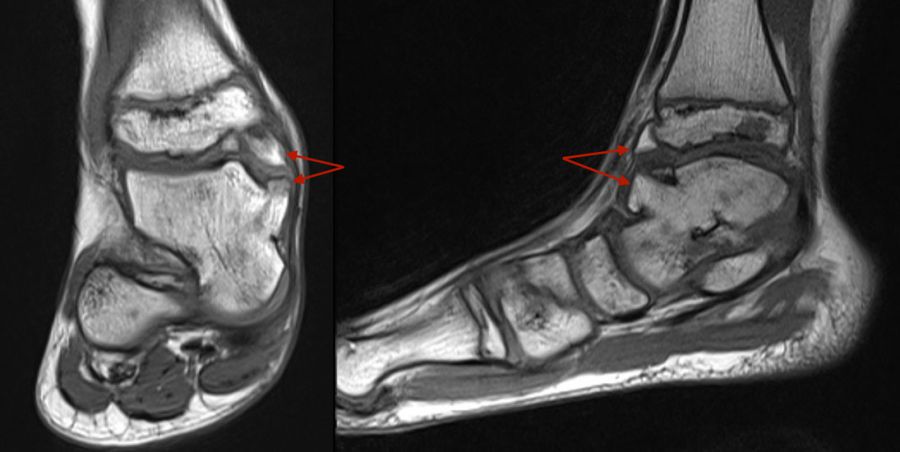

Stellvertretend für gutartige tumoröse Weichteilgeschwulste soll hier die pigmentierte villo-noduläre Synovialitis (PVNS) als wohl häufigste gutartige Weichteilneoplasie des Fußes erörtert werden. Die PVNS nimmt als einzige Entität in allen größeren Studien zu Fußtumoren einen der drei vorderen Plätze ein. Als Synonym der extra-artikulären Form der PVNS ist der Begriff des teno-synovialen Riesenzelltumors gebräuchlich. Die sehnenscheiden- und gelenkkapselreiche Fußanatomie prädestiniert für die Entstehung einer PVNS (Abb. 32). Das weibliche Geschlecht ist doppelt so häufig betroffen, das bevorzugte Alter liegt zwischen 30-50 Jahren. Eine schmerzlose, nur langsam größenprogrediente Schwellung ist das häufigste Symptom. Die Rezidivrate wird mit bis zu 30% angegeben 49. Bei der PVNS handelt sich um einen fibro-histiozytären Tumor (echte Neoplasie) und nicht wie ehemals angenommen um ein inflammatorisches oder posttraumatische Geschehen. Für die intraartikuläre Form, die wiederum in eine noduläre/lokalisierte und diffuse Form unterteilt werden kann, stellt das Sprunggelenk die dritt-häufigste Lokalisation am gesamten Körper dar (Abb. 33).

Im Röntgen zeigt sich gelegentlich eine gut abgrenzbare Weichteilformation (bei nodulärer Form) und knöcherne Druckarrosionen der angrenzenden Knochen. Sekundäre arthrotische Veränderungen der angrenzenden Gelenke sind möglich. Die MRT kann mit einem stark T2-gewichtetem Gradientenecho sog. Suszeptibilitätsartefakte der Hemosiderin­ablagerungen darstellen. Diese führen gewöhnlich zu charakteristischen Signalaus­löschungen in T1 und T2 gewichteten Sequenzen. Eine Kontrastmittel-Aufnahme erfolgt in der Regel diffus und inhomogen. Die Therapie besteht in einer offenen Resektion. Wir raten dringend davon ab, intraartikuläre, lokalisierte Formen der PVNS per Arthroskopie resezieren zu wollen. Dieser Tumor sollte, wenn möglich, marginal und nicht intraläsional reseziert werden. Eine arthroskopische Zerkleinerung mit dem Shaver würde aus einer nodulären Form eine diffuse Form produzieren und die Rezidivwahrscheinlichkeit deutlich steigern. Ebenso ist vor einer Radiosynoviorthese (RSO) bei Vorliegen einer nodulären Variante abzuraten. Bei diesem nuklearmedizinischen Verfahren, welches gewöhnlich Anwendung bei chronisch entzündlichen Gelenkerkrankungen findet, werden Beta-Strahler in Gelenke injiziert. Ein therapeutischer Effekt hat sich bisher nicht nachweisen lassen.